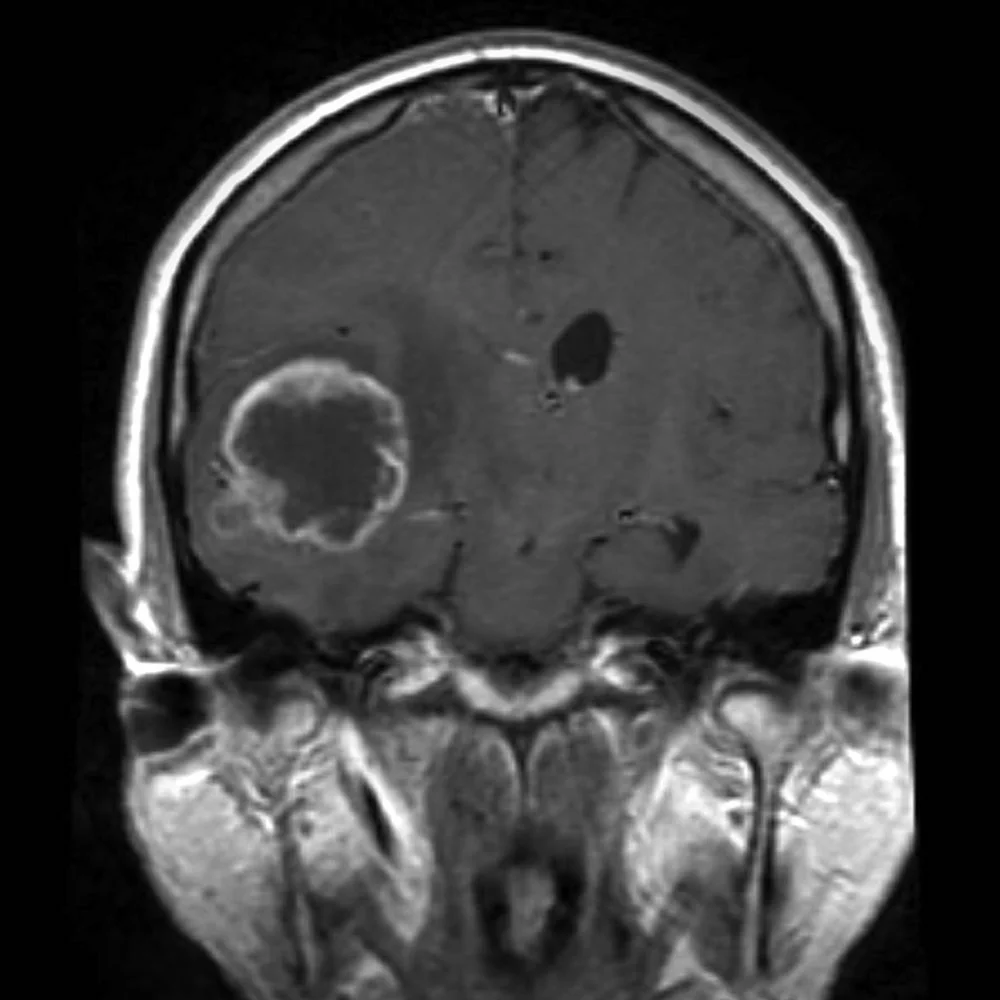

The International Agency for Research on Cancer, an arm of the World Health Organization, made headlines by classifying cell phones as possibly carcinogenic to humans, based on an increased risk for glioma (a type of brain tumor).

Brain Cancer & Cell Phones